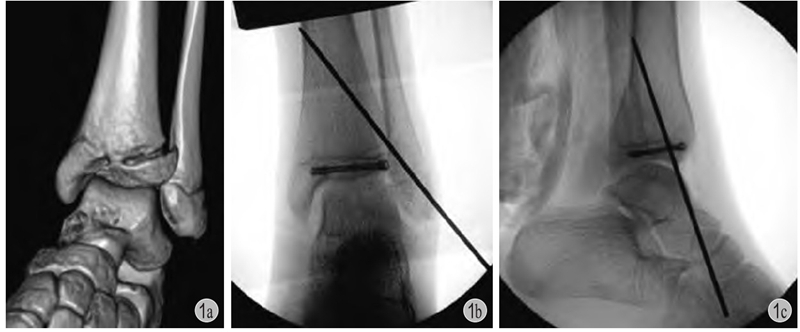

5.螺钉:1850年,法国医师 Cucel 和 Rigaud 首次将螺钉应用于临床,经皮固定治疗鹰嘴骨折。之后,随着内固定材料和医学的进步,螺钉逐渐在临床应用,经过 Hansmann、William 以及 Danis 和 Müller 师徒近一个世纪的发展与改良,形成了目前临床上使用较多的AO系统螺钉。螺钉种类多样,常用于儿童的单独使用的螺钉主要包括金属加压空心钉和可吸收钉或棒,由于加压特点不同金属螺钉又分为全螺纹螺钉和半螺纹螺钉,全螺纹螺钉因不同螺距进行加压,半螺纹螺钉利用头端膨大部位进行加压。螺钉适应证主要有骨骺和干骺端骨折、关节内骨软骨骨折、牵拉骨骺的撕脱骨折以及脊柱矫形、骨盆截骨处固定等,也可应用于生长导向治疗。一般而言,螺钉禁止穿越骺板固定。加压螺钉临床应用广泛,比如儿童胫骨远端骨骺骨折时,可使用空心螺钉平行骺板加压固定 (图1);股骨颈骨折、股骨头骨骺滑脱时,可使用半螺纹或全螺纹变距螺钉加压固定;髋关节发育不良行三联截骨时,也可用全螺纹螺钉固定髂骨截骨端。可吸收钉棒系统主要用于关节内骨软骨骨折、牵拉骨骺撕脱骨折等,虽然可降解不用二次手术取出,但固定牢固性相对于金属螺钉弱,需要术者有所考虑。膝关节等关节面骨折可选用多枚可吸收棒固定,临床效果尚可。金属螺钉置入时要考虑取出时容易寻找,尤其是全螺纹无头空心钉。青少年股骨颈骨折及股骨头骨骺滑脱术后2年以上取螺钉会较为困难,可以早些取或者不取出。

图1 患儿 女12岁

a:左胫骨远端三平面骨折;b、c:切开复位,空心钉+克氏针固定,空心钉平行骺板且位于骨骺内,辅以斜行克氏针穿越骺板固定